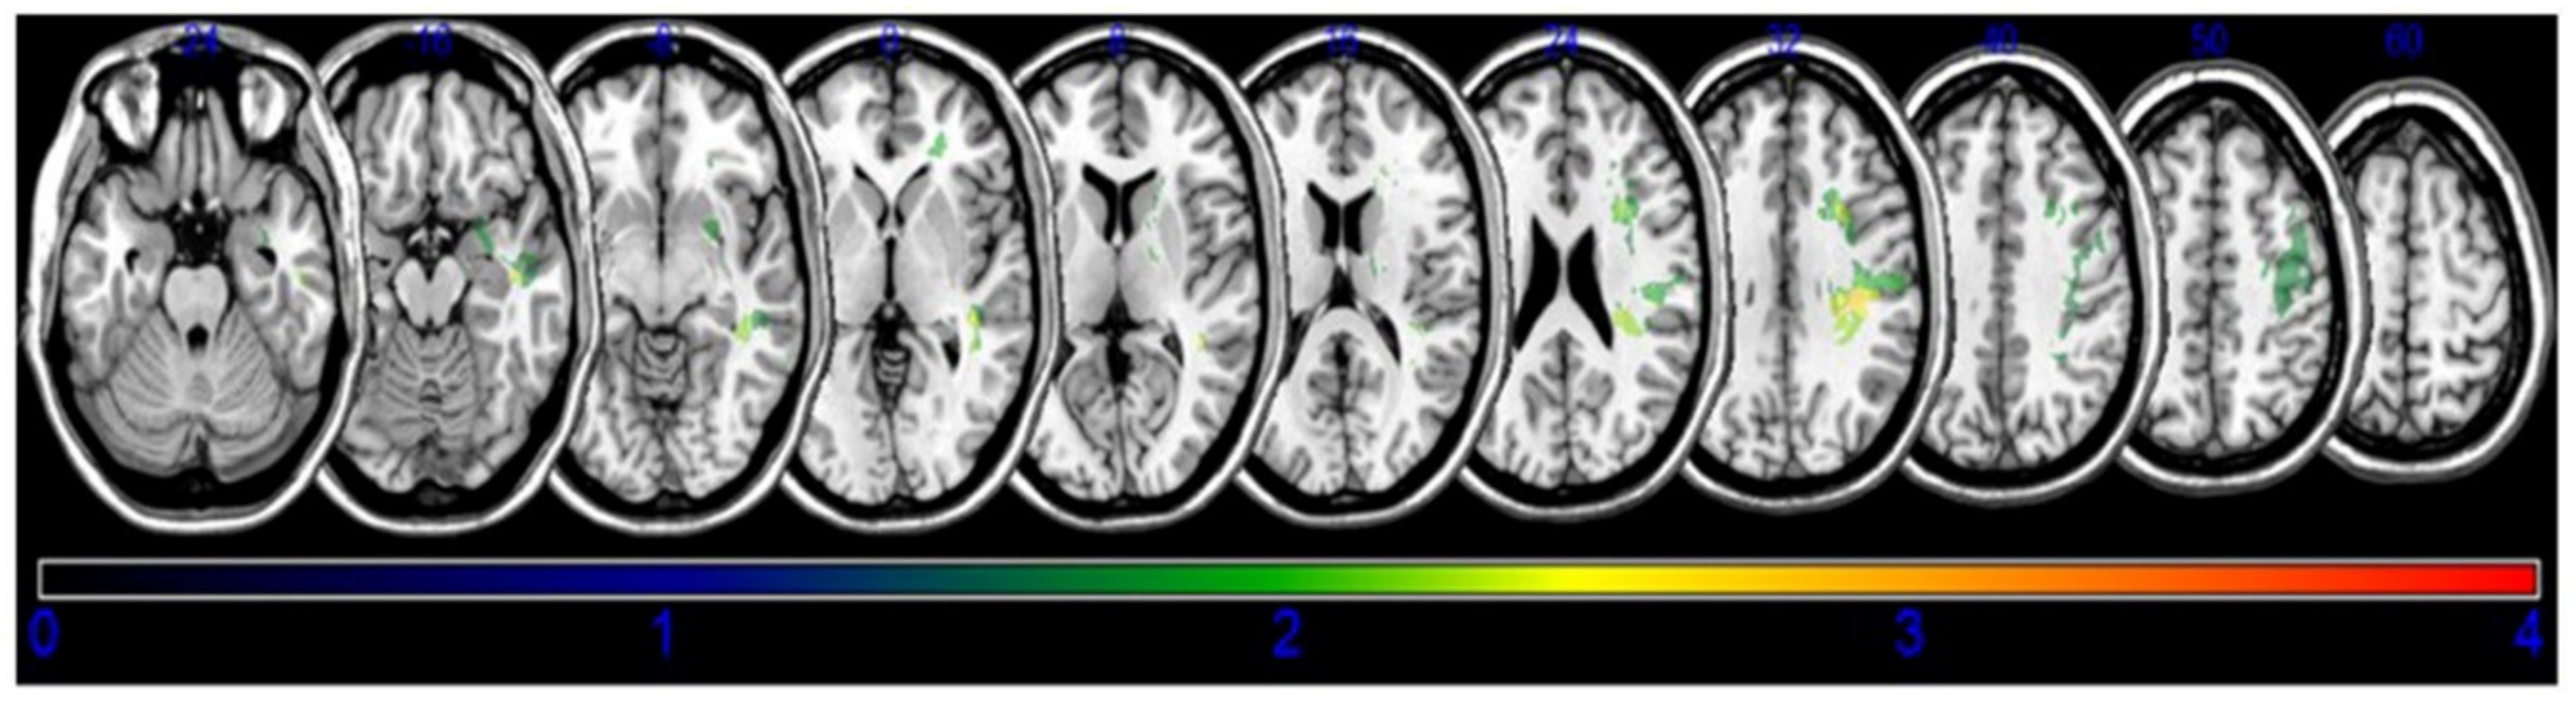

3.2. Lesion Analysis

| MNI Coordinates (X, Y, Z) | BM Z max | n Voxels | Anatomical Brain Lesion |

|---|---|---|---|

| 34, −38, 35 | 2.90267 | 114 | Parietal lobe, Sub-Gyral |

| 29, −26, 32 | 3.38958 | 111 | Frontal lobe, Superior longitudinal |

| 29, 13, 28 | 2.85527 | 116 | Frontal lobe, Sub-Gyral |

| 29, −27, 30 | 3.17468 | 114 | Posterior corona radiata |

| 38, −35, 15 | 2.65207 | 106 | Temporal lobe, STG |

| 42, −41, −7 | 2.55235 | 115 | Temporal lobe, MTG |